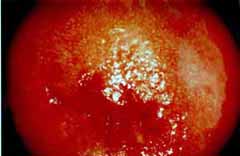

Κολποσκοπικές εικονες για τις αναγκες του forum.